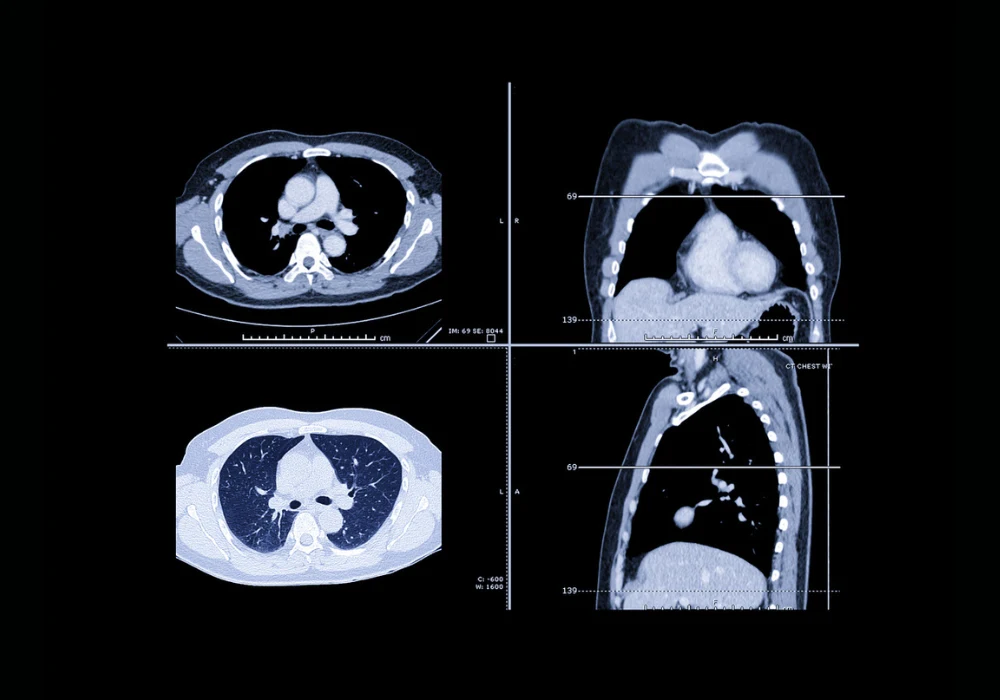

Lung cancer is the leading cause of cancer mortality worldwide, primarily due to late-stage diagnoses. The introduction of low-dose computed tomography (LDCT) screening has proven effective in detecting lung cancer at earlier stages, significantly improving survival rates. Targeting high-risk populations—particularly current or former smokers—screening with LDCT has been validated through major studies such as NLST and NELSON. However, for LDCT screening to reach its full potential, precise and standardised pulmonary nodule management is essential. To this end, the European Society of Thoracic Imaging (ESTI) has proposed a refined classification system for screen results and recommendations for managing pulmonary nodules, aiming to balance early cancer detection with minimised overdiagnosis and unnecessary follow-up.

Volumetric assessment, particularly measuring volume doubling time (VDT), is increasingly preferred over manual diameter measurements due to its superior precision. A 100% increase in volume corresponds to only a 26% increase in diameter, making subtle growth more detectable with volumetry. It also captures asymmetric growth, especially in the z-axis, that diameter-based methods may miss. Nevertheless, volumetry has limitations, especially when segmenting subsolid or cystic nodules, or those adjacent to anatomical structures like the pleura or blood vessels. Factors such as scan reconstruction parameters, patient positioning and respiratory motion can also affect volume measurement reliability. Consistency in software and scanning technique is thus critical to ensuring accurate growth assessment.

The ESTI guidelines recommend specific flowcharts for managing solid and subsolid nodules detected at baseline, during follow-up and when newly observed. At baseline, nodules are classified by morphology, density and size. Nodules with benign features such as calcifications or typical intrapulmonary lymph node morphology are considered negative and managed with annual screening. Nodules showing suspicious features or exceeding certain volume or diameter thresholds enter the indeterminate or positive categories and require short-term follow-up or diagnostic work-up.